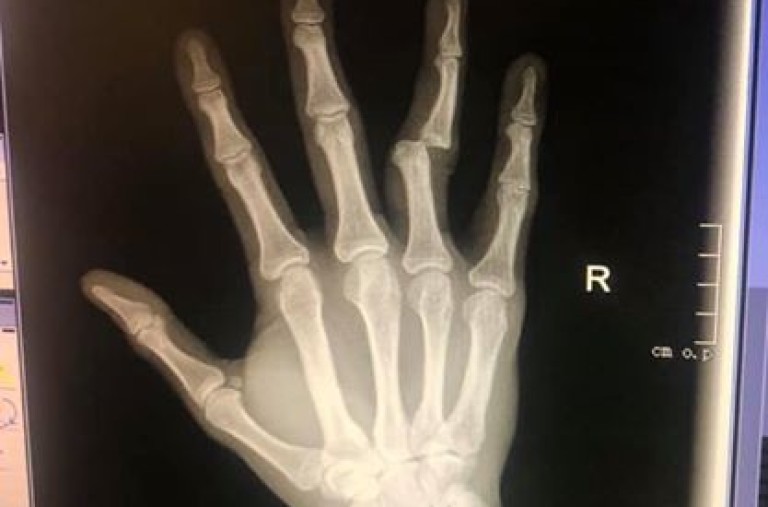

Антон Петров, който е световен шампион по муай тай за професионалисти във версия WMC, публикува снимка в социалните мрежи, която показва сериозността на контузията му.